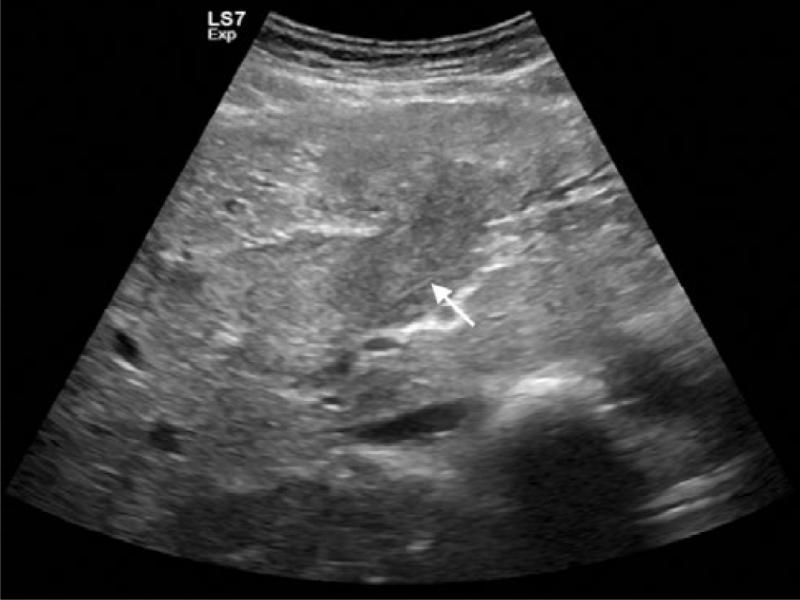

Fig. 1.

Gray-scale US image shows the left portal vein expanded with occlusive tumor thrombus (white arrow)